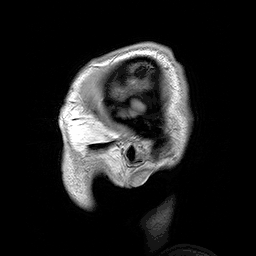

![]() İyi huylu makrosefali hastalığı olan birine ait kafanın para-sajital düzlemden çekilen MRI görüntüsü | |